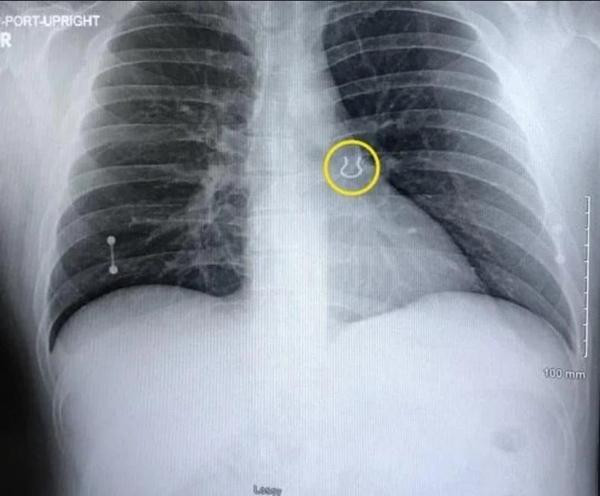

Lo rằng mình bị bệnh đường hô hấp hoặc viêm phổi, sáng hôm sau, Joey tới bệnh viện khám. Hình ảnh X-quang đã cho thấy có một vật thể lạ ở thùy trên của lá phổi trái. Bác sĩ đưa ảnh cho Joey xem. Ngay lập tức, cái vật thể nhỏ và cong đó khiến Joey vô cùng bất ngờ: Nó là cái khuyên mũi đã mất tích từ 5 năm trước!

| "Vật thể lạ" trong phổi của Joey. Ảnh: Facebook. |

Joey kể lại: “Bác sĩ đưa ảnh và hỏi tôi: “Thứ đó trông có quen không?”. Tôi gần như kêu lên: “Tôi đã tìm nó suốt mà không thấy!”. Tôi không bao giờ có thể nghĩ là nó lại ở vị trí đó được!”.

Vậy hóa ra là Joey đã hít cái khuyên mũi vào trong tận phổi khi anh ngủ. Đúng là chuyện khó tin nhưng thực sự đã xảy ra.